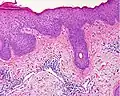

Als Reaktion auf den anhaltenden Entzündungsreiz und juckreizbedingtes Kratzen kommt es in der Folge zur Verbreiterung der Epidermis (Akanthose) mit Rückgang der Spongiose. Anfangs eventuell vorhandene größere Blasen gehen zurück, und es verbleiben nurmehr kleine Bläschen. Zumeist besteht jetzt eine ausgedehnte Parakeratose, und im Randbereich oberflächlicher epidermaler Defekte (Erosionen) können auch neutrophile Granulozyten (Untergruppe der weißen Blutkörperchen) in der Epidermis zu sehen sein. Dieses Zwischenstadium wird gelegentlich auch als subakute Phase bezeichnet.

Chronische Phase: es überwiegen die Zeichen der chronischen mechanischen Irritation mit Lichenifikation: epidermal zeigt sich eine deutliche Akanthose mit Verbreiterung der Granularzellschicht (Hypergranulose) und Hyperkeratose. Die Spongiose geht weiter zurück und kann in diesem Stadium nur noch sehr schwach ausgeprägt sein. Das der Epidermis unmittelbar unterliegende Bindegewebe der oberen Dermis (Stratum papillare) zeigt eine Vermehrung von Kollagenfasern (Fibrose), die senkrecht zur Epidermis ausgerichtet sind.[5]

Hyperkeratose: der Epidermis aufgelagert besteht eine verbreiterte Hornschicht. In der Dermis Kapillaren mit umliegenden Entzündungszellen

Parakeratose: die Hornschicht enthält Reste von Zellkernen als Zeichen der gestörten Verhornung